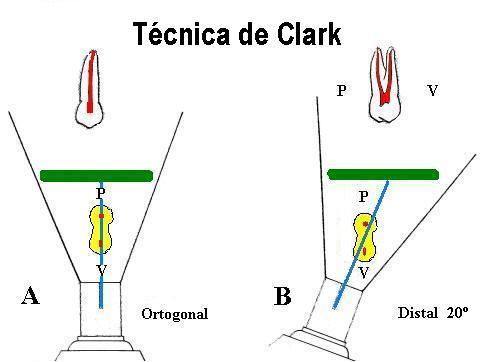

2-

Disposición, grado de curvatura y número de conductos radiculares

La radiografía periapical es la proyección de un objeto

tridimensional sobre una película bidimensional, por

lo tanto observará una superposición de imágenes que

debe ser interpretada.

Por ejemplo usted realiza una radiografía periapical del

14 con una dirección del rayo ortogonal (A) lo

cual determinará una superposición de imágenes entre la raíz

vestibular y palatina.

Pero como conoce por estadística que

más del 75% de los

primeros premolares superiores tienen un conducto el la raíz vestibular y

otro en la palatina. Decide realizar lal

"Técnica de Clark" que consiste desplazar el

rayo central en forma horizontal unos 20º hacia distal

o mesial

(B) Ambas raíces se desplazan en el mismo

sentido. La raíz que esta más próxima a la radiografía

será la que se desplace menos. En el caso del ejemplo de de

la derecha la raíz vestibular se desplaza más hacia mesial.

Y por lo tanto verá en la radiografía la separación de ambos

conductos. Ver imagen inferior

7.

Para conductos que se superponen es necesario

realizar la técnica de doble incidencia o

técnica de Clark, para desproyectar a los

conductos vestibulares del palatino o lingual.